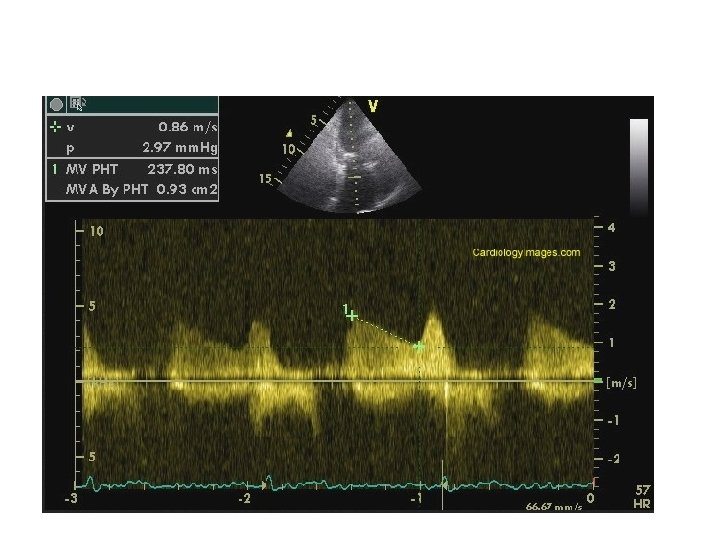

Pressure half-time (PHT) • PHT is defined as time interval in msec between maximum mitral gradient in early diastole & time point where the gradient is half the maximum initial value. • Decline of the velocity of diastolic transmitral blood flow is inversely proportional to valve area. • MVA is derived using the empirical formula MVA = 220/PHT

Pressure half-time • In addition to MVA , PHT depends on net compliance of LA & LV and square root of maximum transmitral gradient. • PHT obtained by tracing the deceleration slope of E-wave on Doppler spectral display of transmitral flow.

Measuring T 1/2 with a bimodal slope of Ewave Deceleration slope in mid-diastole rather than early to be traced

MS with AF pts Tracing should avoid mitral flow from short diastoles and average of different cardiac cycles to be taken

Factors affecting PHT LA pressure decline Ø ASD : LA draining to second chamber. Ø Stiff LA – low LA compliance LA pressure drop rapidly and PHT is shortened. LV pressure rise Ø AR : LV fills from a second source. Ø Stiff LV (stiff-low ventricular compliance) LV pressure may rise more rapidly and PHT will be shortened. All these results in overestimation of MVA

PHT after BMV • PHT is inaccurate soon after acute valvotomy. • Usually increase in mean gradient is compensated by decrease in compliance. • Immediately after BMV there is discrepancy between decrease in mitral gradient and increase in net compliance.